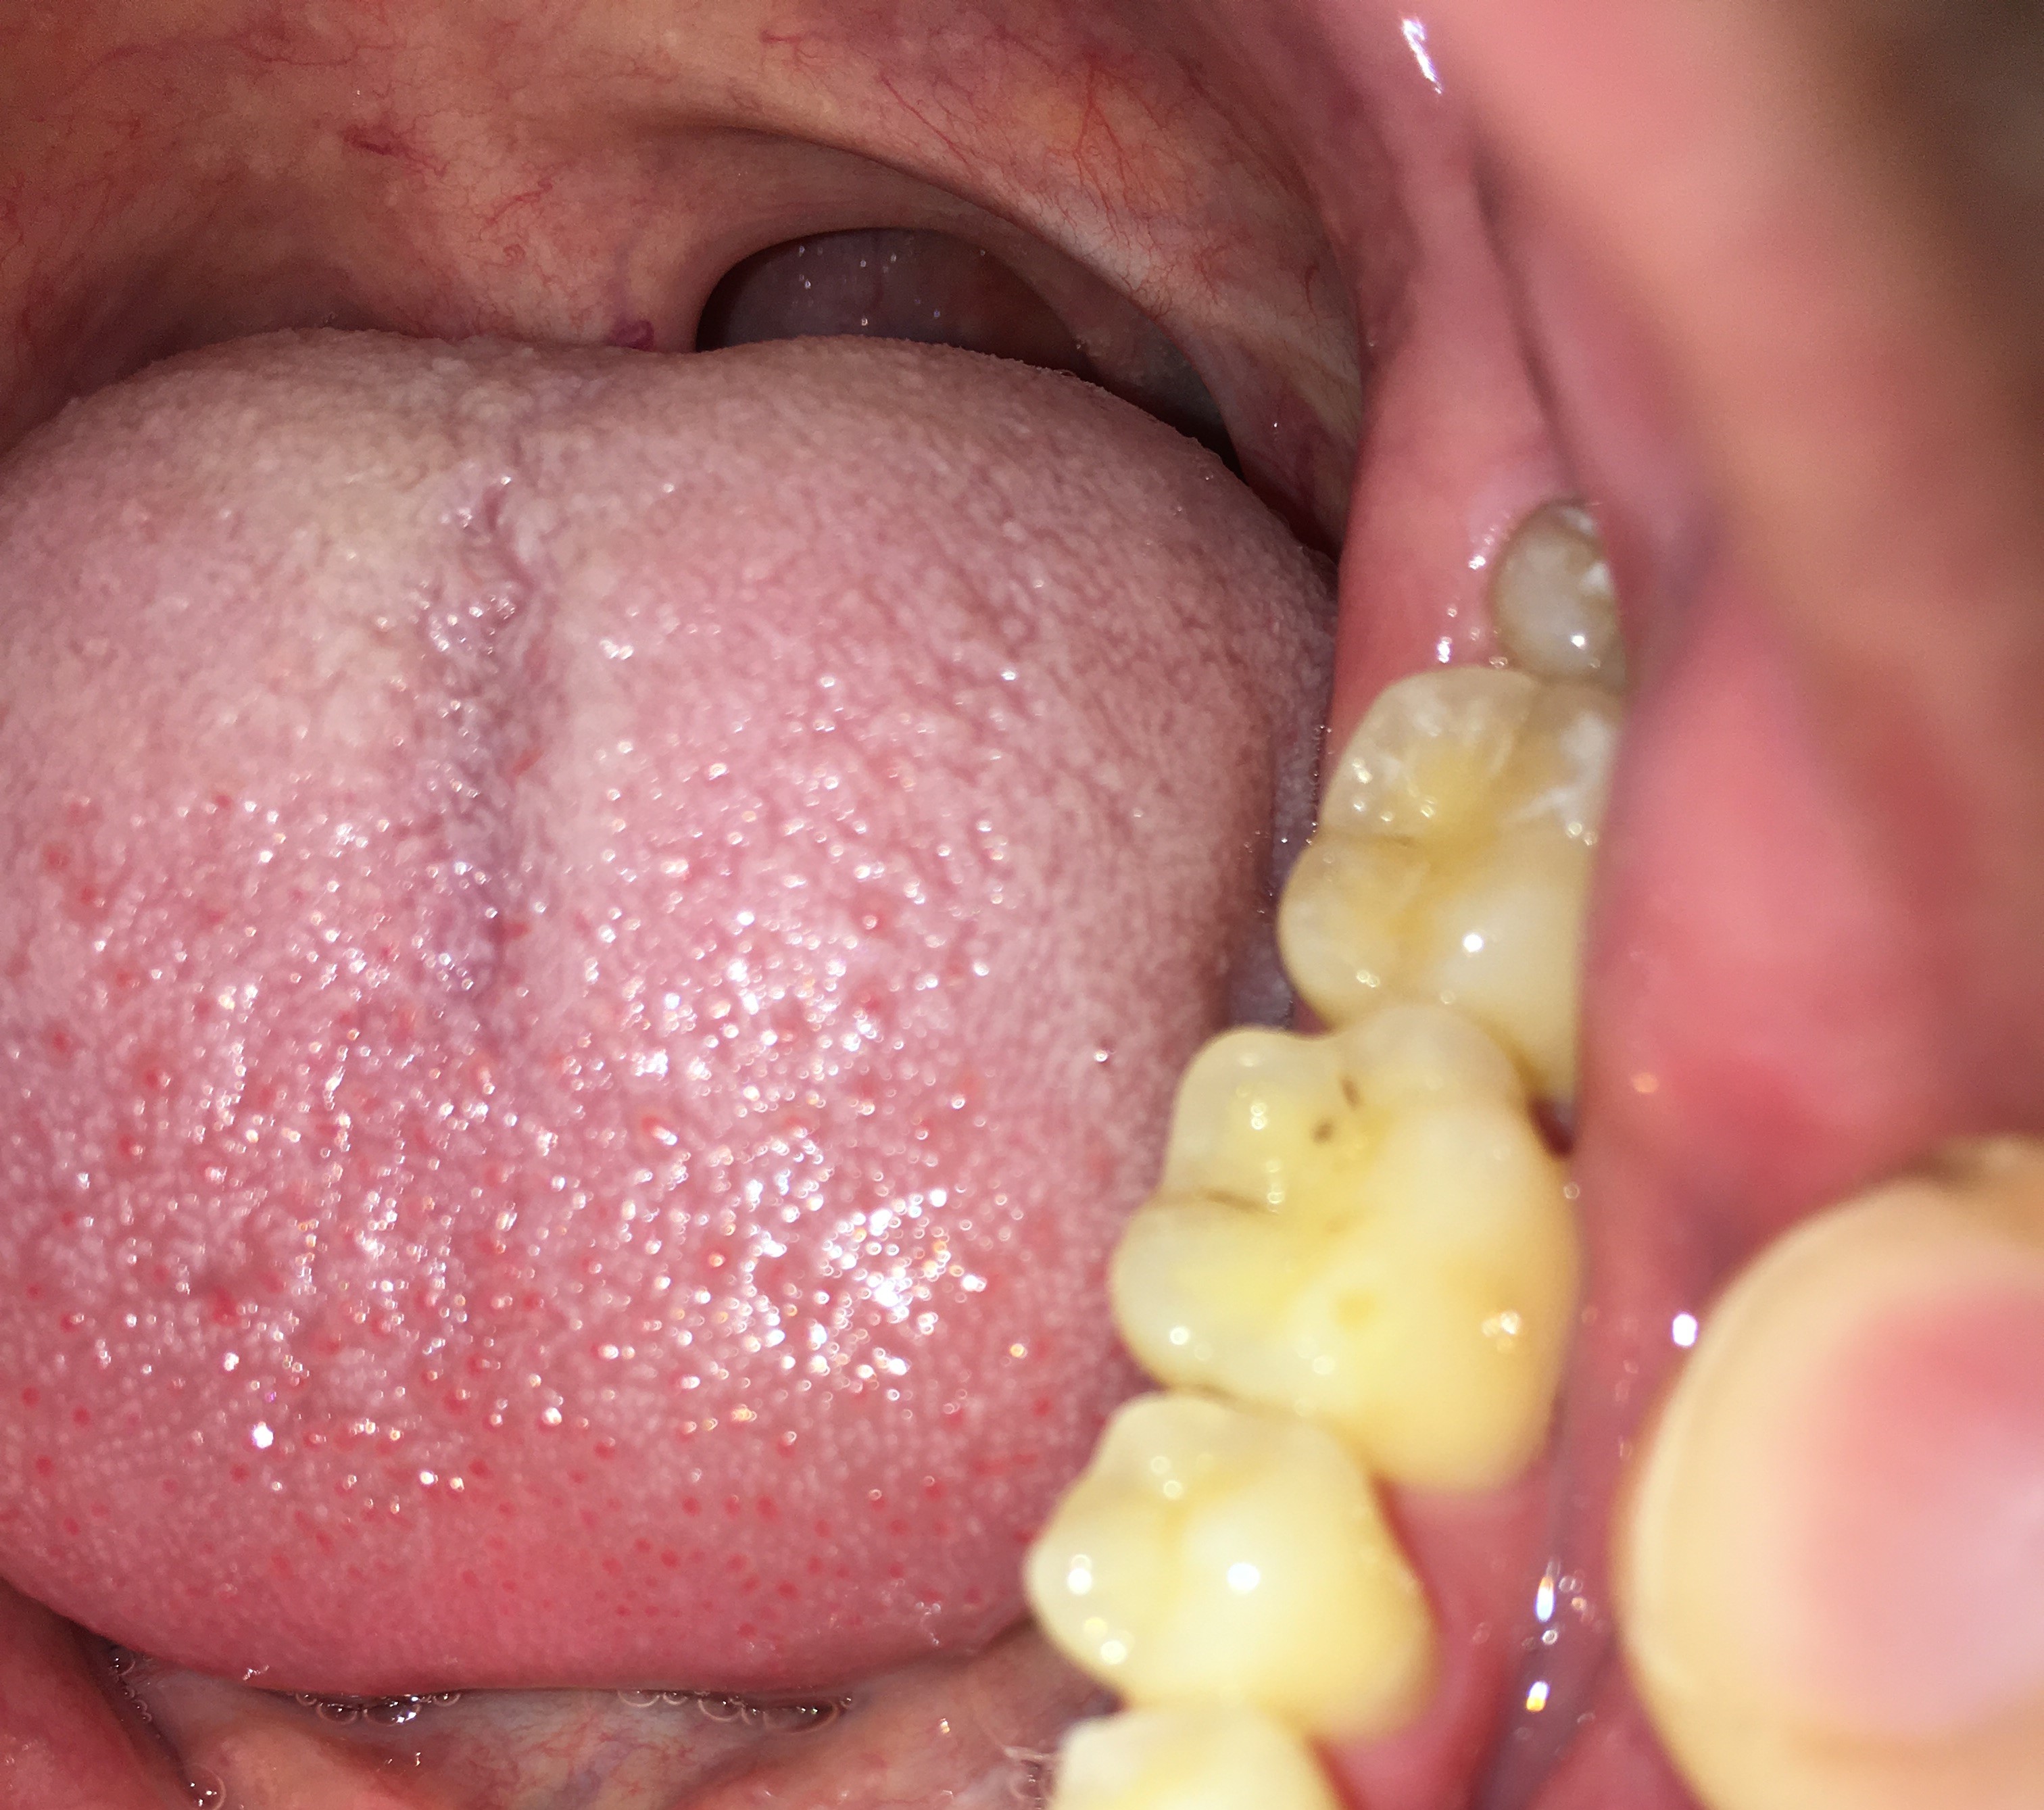

Hierbij 3 foto's van mijn onderkaak. De eerste foto is van mijn linker onderkaak van 2017, de tweede foto is van mijn rechter onderkaak van 2017 en de laatste foto is van 2015 van mijn gehele onderkaak. De foto van 2015 is met een andere telefoon genomen, hierdoor is de kleur en belichting wat anders, echter zie ik bij alle drie de foto's en de foto van 2025 de zelfde hoeveelheid doorzichtigheid.